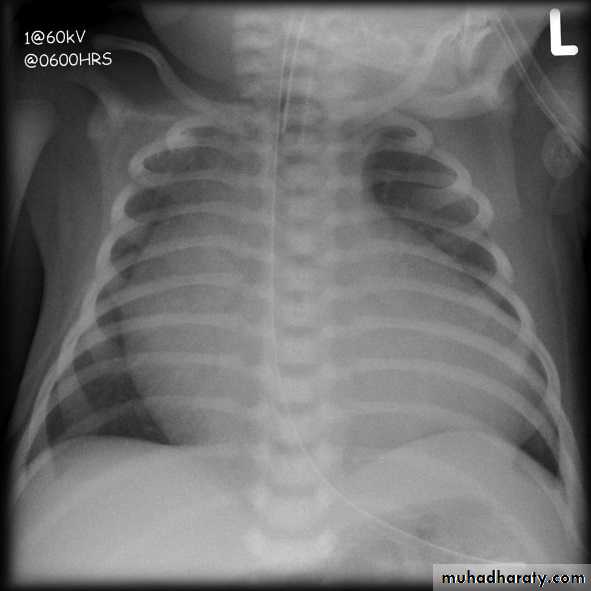

Cardiothoracic ratio (CTR) = Cardiac Width : Thoracic Width

A CTR of greater than 1:2 (50%) is considered abnormal. This however, assumes the projection is Posterior-Anterior (PA), and that cardiac size is not exaggerated by factors such as patient rotation or an incomplete breath in .

The cardiothoracic ratio aids in the detection of cardiomegaly, or more broadly, HYPERLINK "http://radiopaedia.org/articles/enlargement-of-the-cardiac-silhouette" enlargement of the cardiac silhouette.